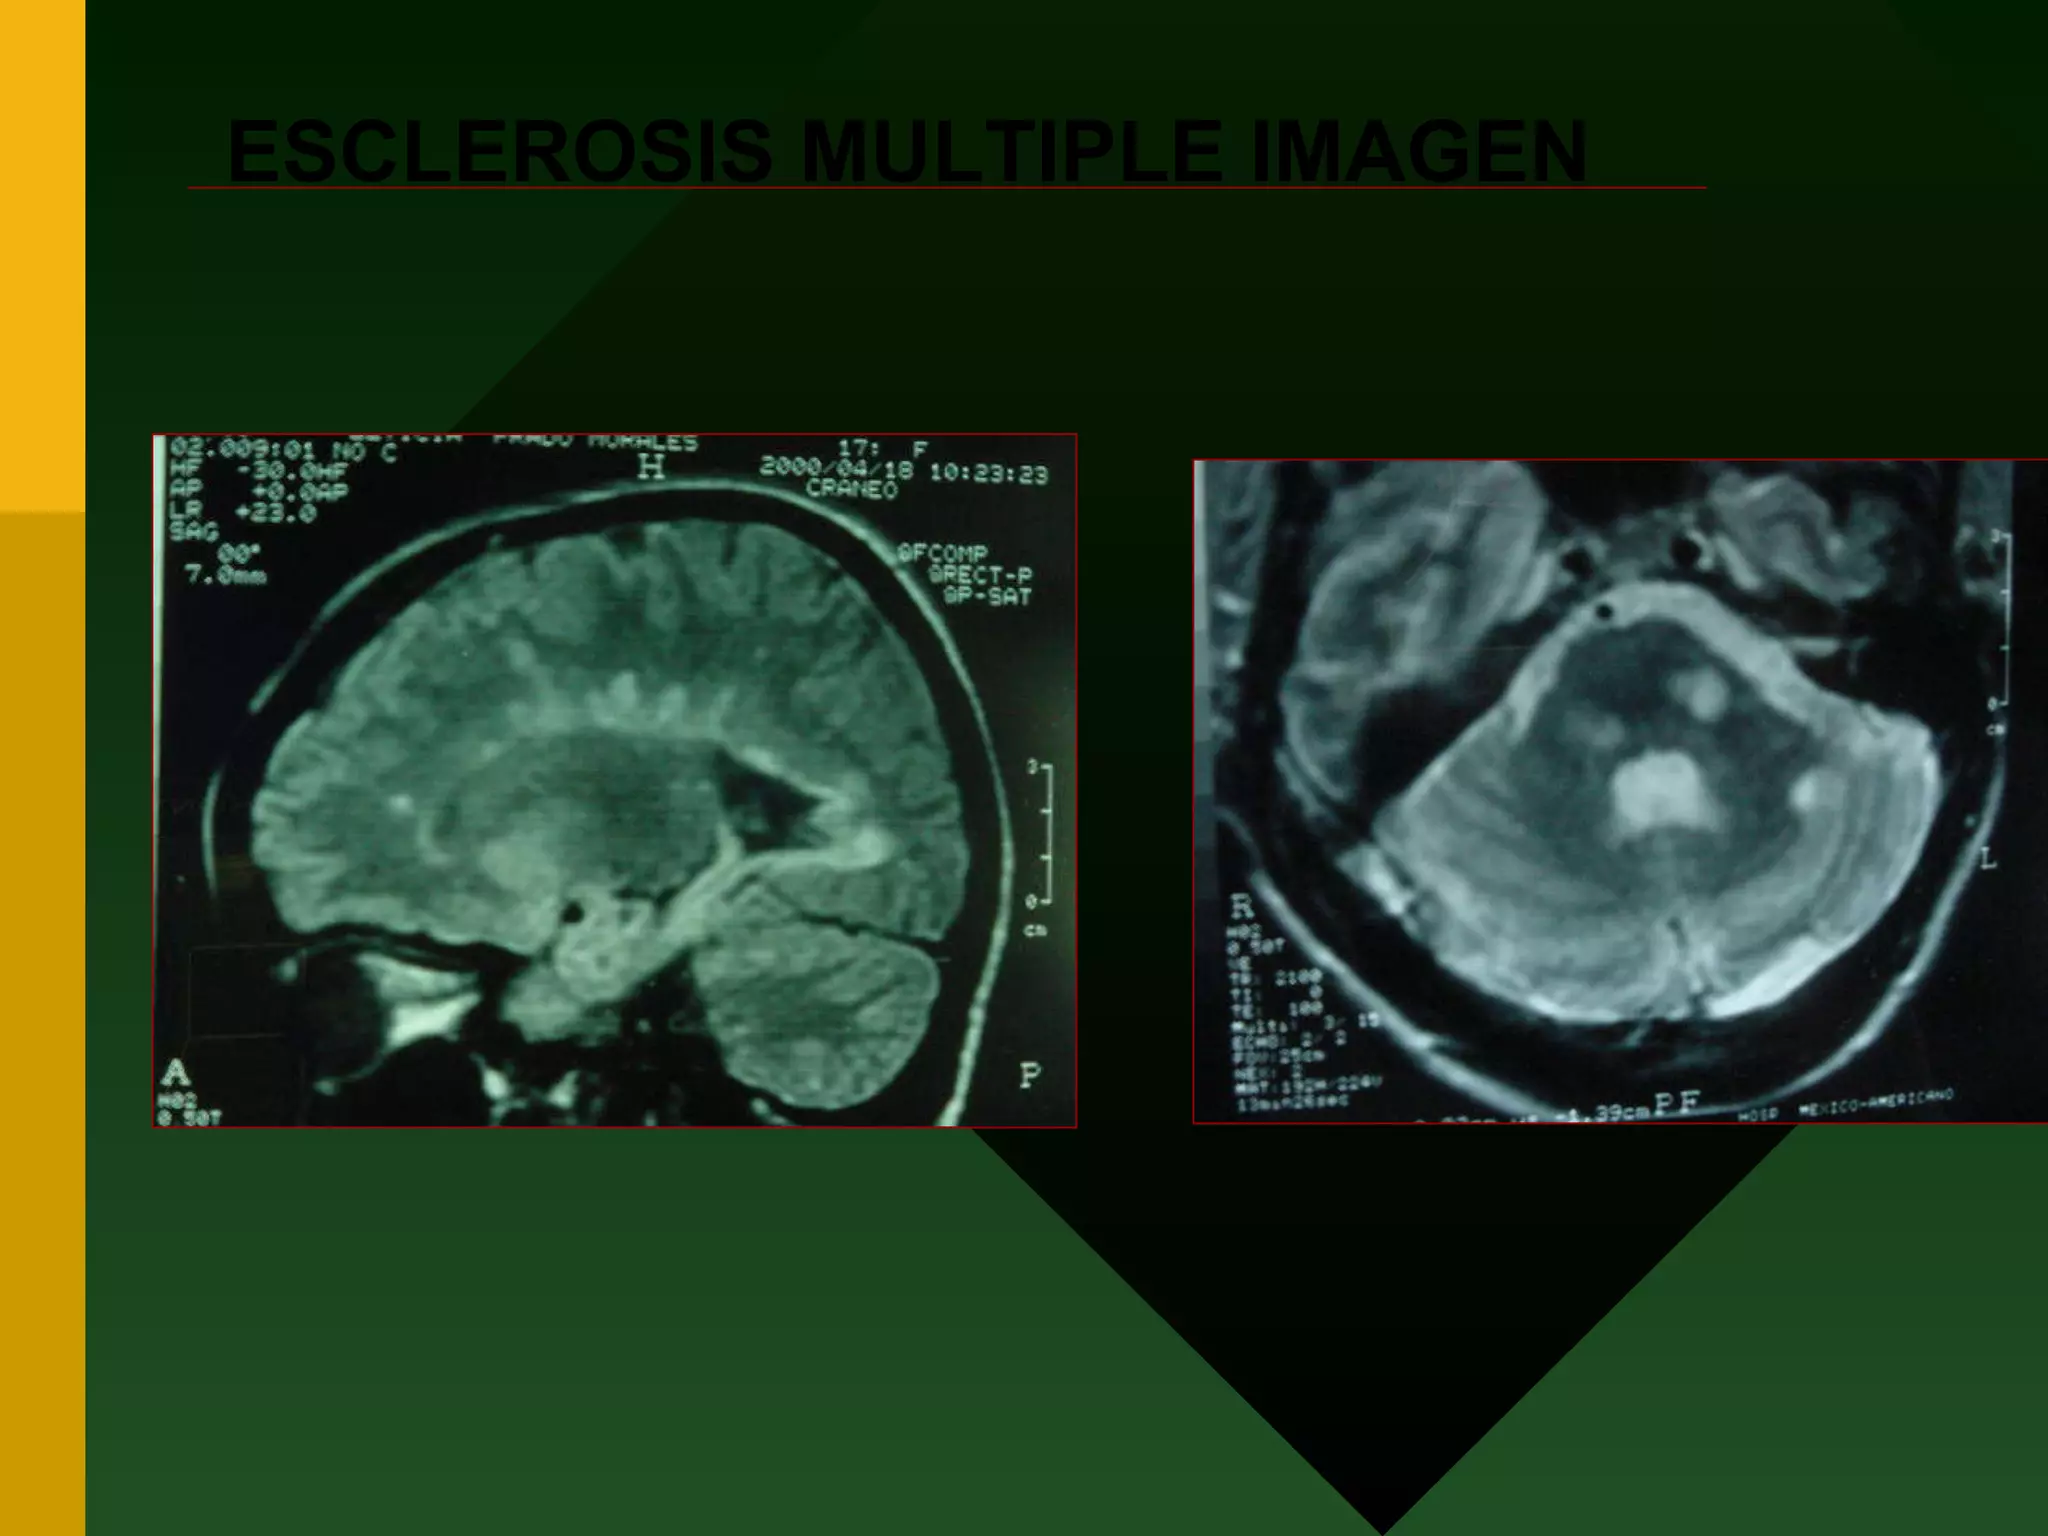

CRITERIOS DIAGNOSTICOS RADIOLOGICOS CRITERIOS DE BARKHOF Y TINTORE TRES DE LAS SIGUIENTES Lesión que refuerce al gadolinio o 9 hiperintensas Al menos tres periventriculares Al menos una en fosa posterior y/o médula Al menos en unión cortico-subcortidal

ESCLEROSIS MULTIPLE IMAGEN

CRITERIOS DIAGNOSTICOS RADIOLOGICOSCRITERIOS DE BARKHOF Y TINTORE TRES DE LAS SIGUIENTES Lesión que refuerce al gadolinio o 9 hiperintensas Al menos tres periventriculares Al menos una en fosa posterior y/o médula Al menos en unión cortico-subcortidal